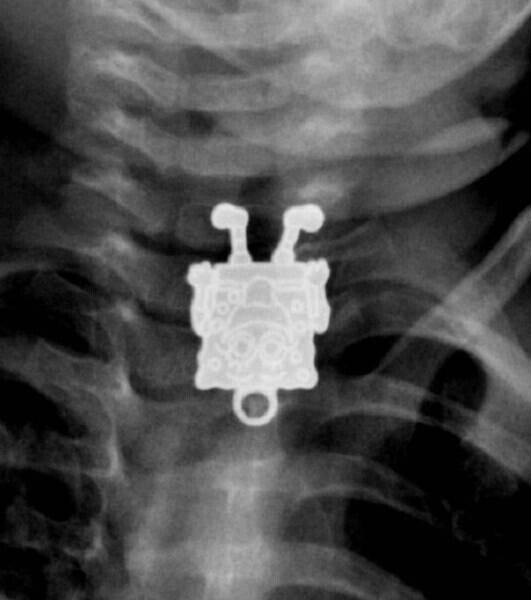

17. Спанч Боб